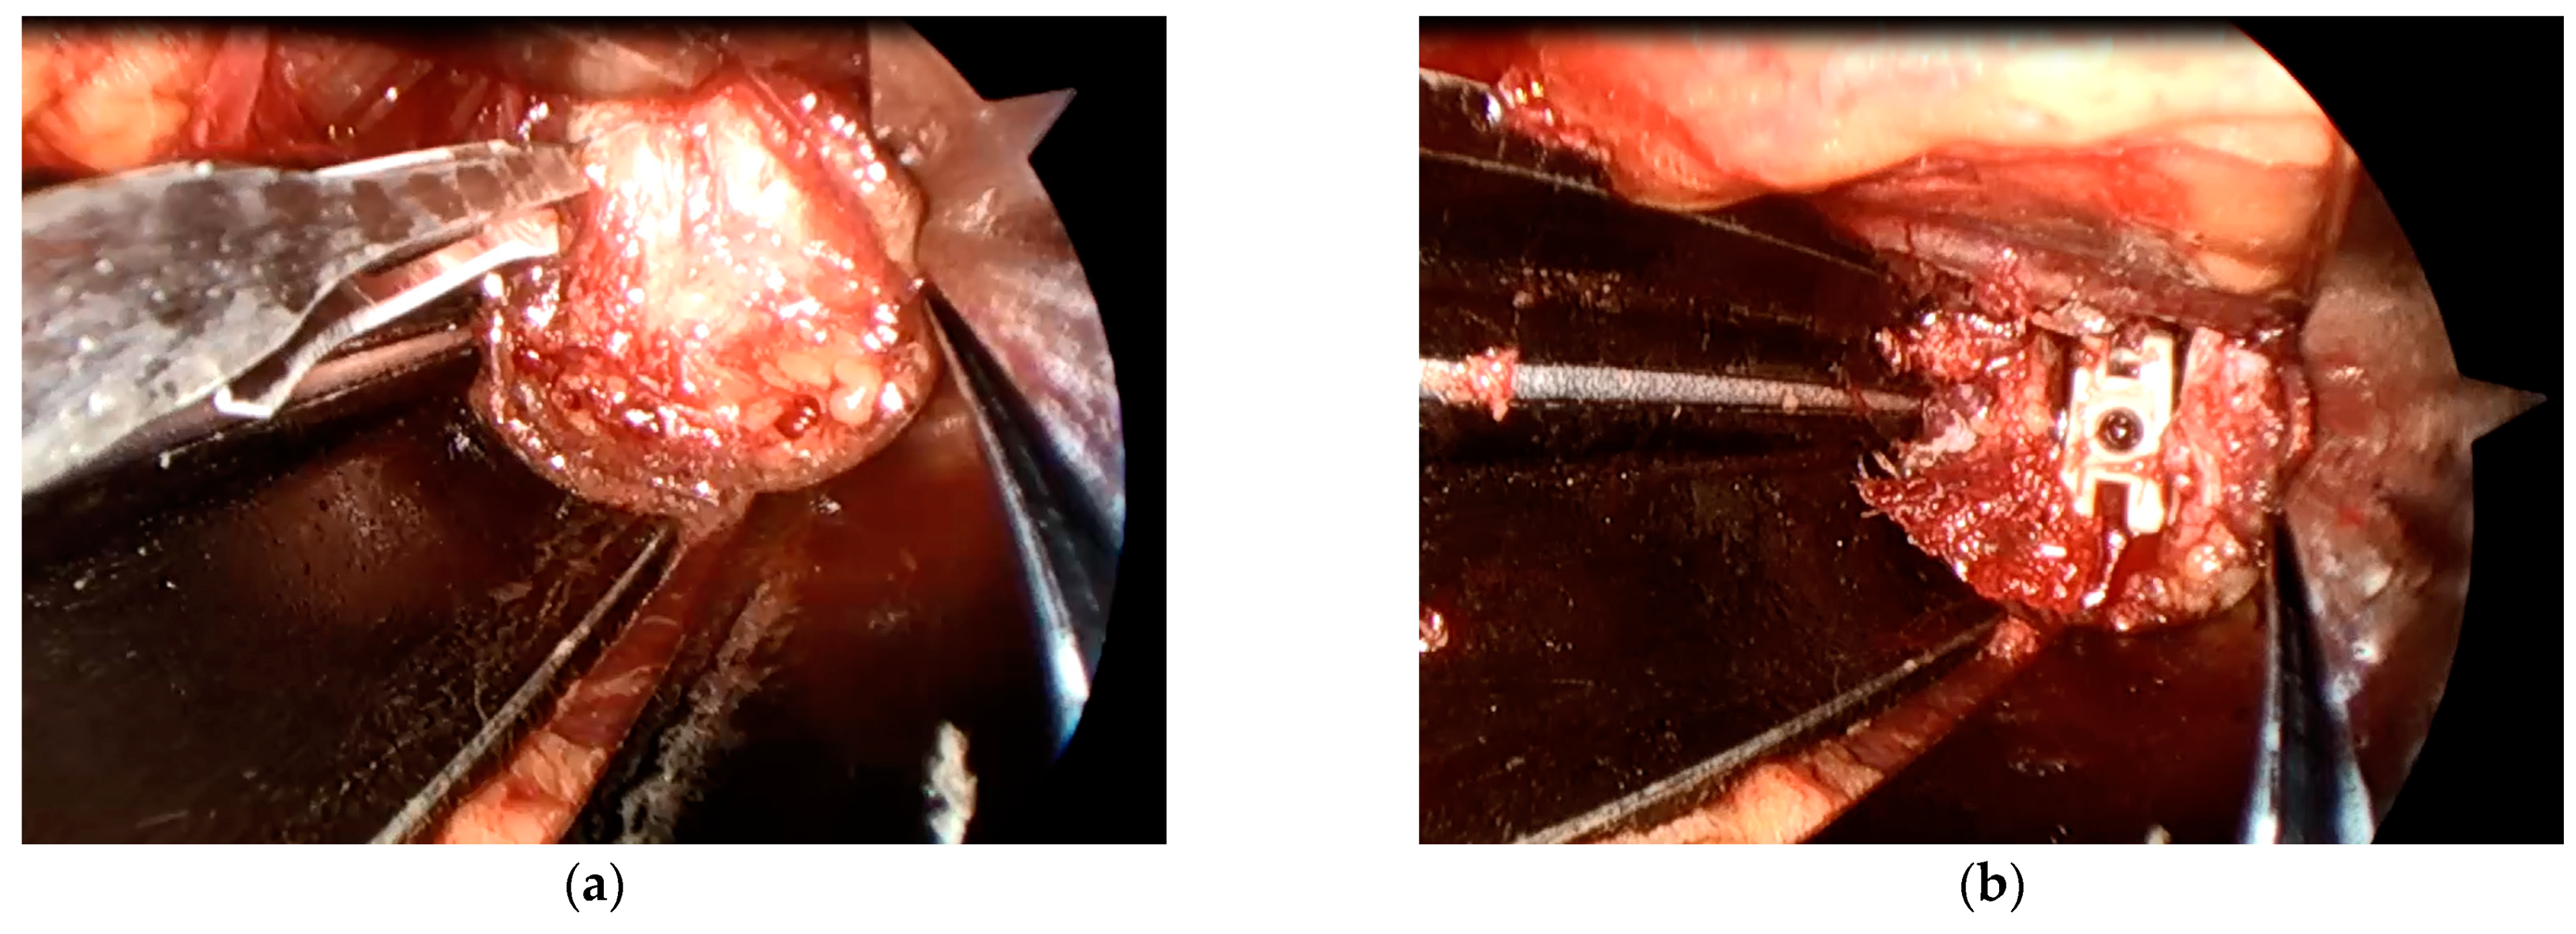

A microendoscope (Medtronic Sofamor Danek, Memphis, TN, USA) was attached to a retractor with a customized attachment (Figure 1). Subsequently, the lateral part of the annulus fibrosis was clearly visualized, incised, and discectomized. Additionally, an interbody implant placement was performed (Figure 2). Following anterior fusion, patients were prone to undergo posterior fusion with pedicle screws via percutaneous procedures.

Microendoscopy-assisted spine surgery is widely practiced in Japan as a minimally invasive technique [26] and was first applied to lumbar disc herniation [27]. A more extended application of the technique has been described to perform spinal canal decompression and interbody fusion [28]. There are two major advantages for performing the microendoscopic technique. First, a microendoscopic lens is angled at 25° and the visual field of a microendoscope lies within the body during surgery. Therefore, better visualization of the lateral aspect is achieved compared to the unaided eye or surgical loupes, which are viewed from the exterior of the body (Figure 2). Secondly, the surgeon, assistant, and scrub nurse can simultaneously observe the same surgical field through the microendoscopic view. As a result, the progress of surgery can be accurately assessed in real time to enable a smooth and efficient workflow.

Figure 2. Intraoperative microendoscopic view of the retroperitoneal space. (a) The lateral part of the annulus fibrosis was clearly visualized, incised, and discectomized; (b) an interbody implant placement was performed.